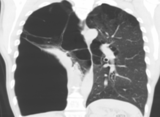

*仅供医学专业人士阅读参考东方呼吸联盟第十一期等你来看~病例简介图1一名慢性阻塞性肺疾病(COPD)并巨大肺大疱伴有II型呼吸衰竭的患者,经吸入性糖皮质激素(ICS)+吸入型长效β2受体激动剂(LABA)+长效抗胆碱能拮抗剂(LAMA)、家庭氧疗等治疗,胸闷仍然频繁发作,患者焦虑、烦躁,每日自行使用超量气道扩张剂,对于这类患者,内科医生该如何处理?患者男性,62岁,住院日期:2021年06月22日。...